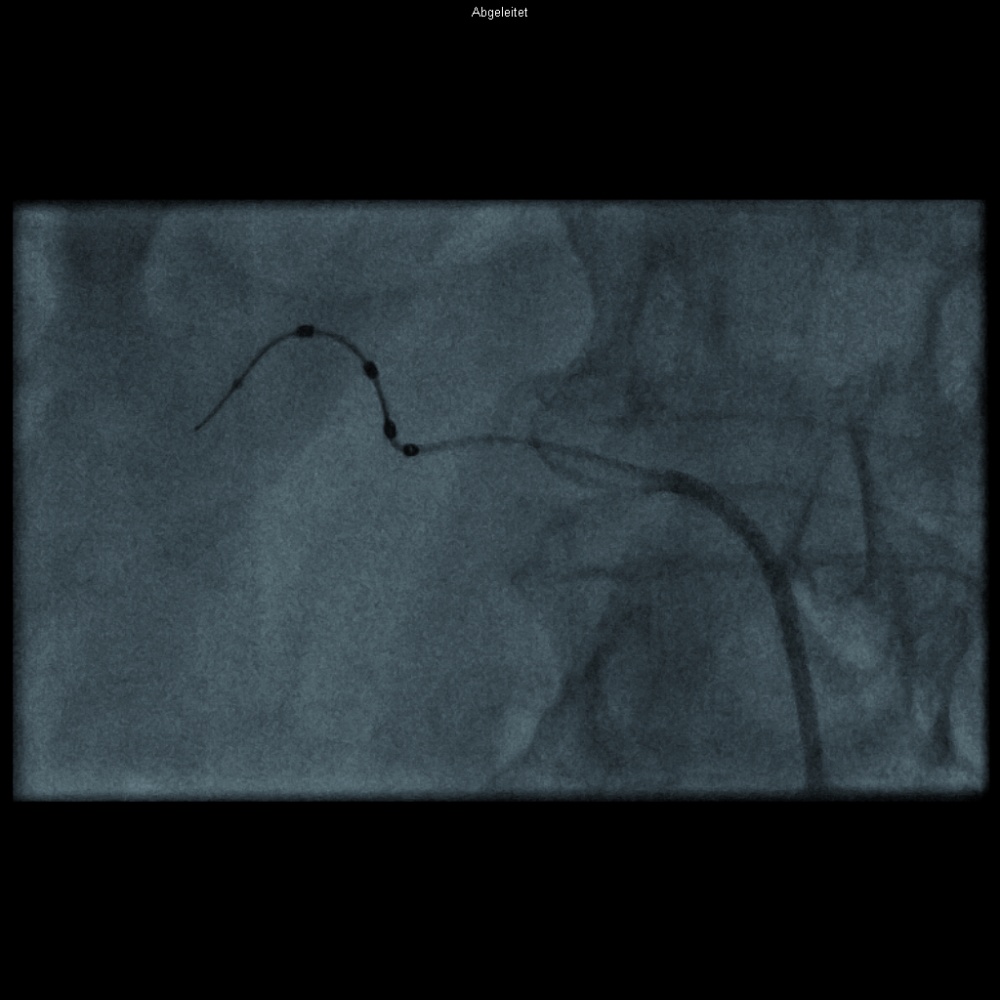

Im Vergleich zu Abbildung 2 sind hier vier Elektroden (dunkel

im Bild) spiralförmig auf einem Katheterdraht angeordnet. (Symplicity

Spyral-Katheter)

WMM_

Neben der Anwendung von Radiofrequenzenergie mittels einer „Single-point-Läsion“ (Abbildung 2) haben sich mehrere verschiedene Techniken entwickelt. So sind auch Katheter verfügbar, welche mit mehreren Elektroden besetzt sind, wie etwa das EnligHTN-System (St. Jude Medical, St. Paul, MN, USA) [23] oder das Symplicity Spyral-System von Medtronic (Min-neapolis, MN, USA) (Abbildung 3) [24]. Ebenso ist eine einmalige, zirkumferenzielle Ablation mittels des Paradise-Systems (ReCor Medical PARADISE® Inc., Palo Alto, CA, USA) möglich. Hierbei handelt es sich um einen gekühlten Ballon mit Nutzung von Ultraschall als Energieform, um die sympathischen Nervenfasern zu veröden [25]. Daneben gibt es noch weitere, weniger verbreitete und weniger erforschte Methoden, wie etwa die Kryoablation [26] oder die Denervation mittels perkutanem Ultraschall [27]. Randomisierte Studien, welche die verschiedenen Systeme in Bezug auf die resultierende Blutdruckreduktion testen, existieren derzeit noch nicht. Bisher wurden allerdings zwei Studien publiziert, bei denen sich ein blutrucksenkender Effekt durch eine zweite Prozedur mit einer anderen Energieapplikationsform zeigte [26, 28].

Abbildung 3: Flottillenarzt Priv.-Doz. Dr. Sebastian Spethmann, BwKrhs Berlin und Charité Berlin, Campus Mitte